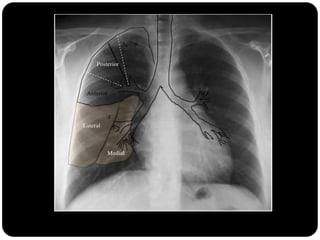

Brônquios segmentares

Pulmão direito

Superior: direito

inferior: esquerdo

Vias aéreas

Traquéia

Brônquios

Bronquíolos

Alvéolos

 Pulmão direito:

 LSD: anterior, apical e posterior;

 LM: medial e lateral;

 LID: superior, basal medial, basal lateral,

basal anterior, basal posterior;

 Pulmão esquerdo:

 LSE: apicoposterior, anterior,

superior(língula), inferior(língula);

 LIE: segmento superior, basal antero-

medial, basal lateral e basal posterior;